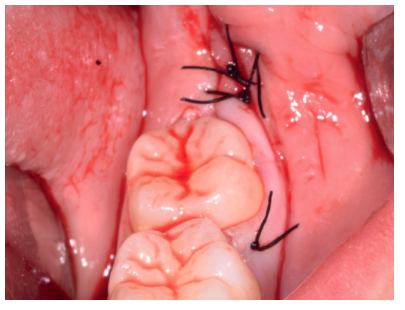

Caso clínico: se presenta un caso clínico de una mujer de 20 años, sin antecedentes médico-quirúrgicos de interés, que acudió a consulta remitida por su ortodoncista, para la extracción de un premolar maxilar retenido, en posición invertida. Tras la extracción del premolar y del tercer molar inferior retenidos, se obtuvo dentina procedente de ambos, para la regeneración ósea guiada del defecto resultante de la extracción del premolar, realizando revisiones a la semana y a los 4 meses de la intervención.

Clinical case: a clinical case of a 20-year-old woman is presented, with no interesting medical record, who went to dental clinic for removal of an inverse maxillary bicuspid retained. After maxillary bicuspid and lower third molar extractions, autogenous dentin was obtained from both teeth, to perform a guided bone regeneration of the bicuspid defect. A week and 4-month check-up were carried out.